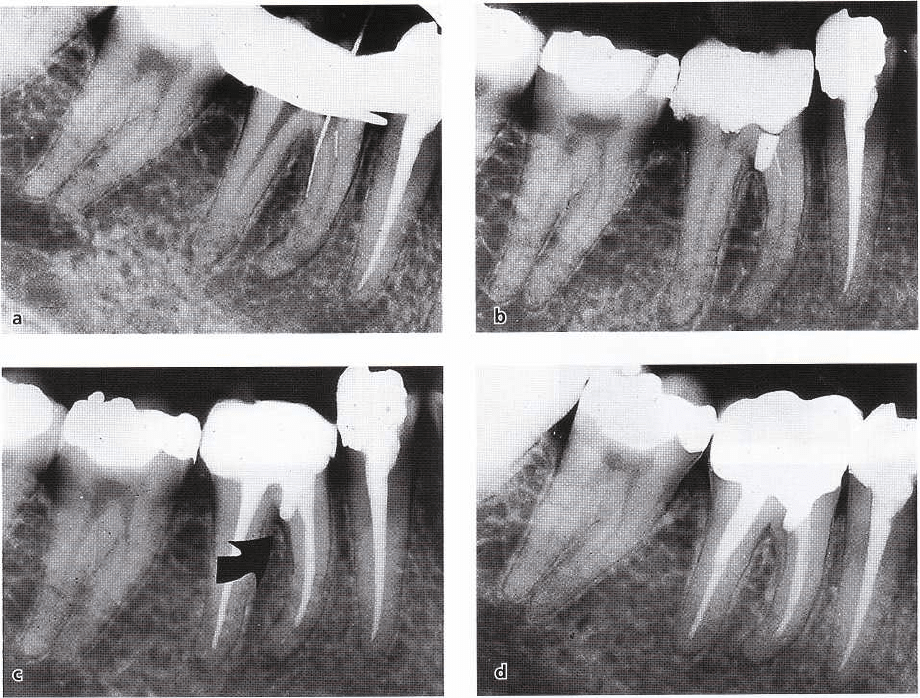

Fig. 14-9. Angular bone defect is observed along the distal root surface of a mandibular canine (a). Apical-

marginal communication was confirmed by periodontal probing (b). Endodontic treatment resulted in complete

reestablishment of the periodontal structures, demonstrating that the periodontal defect in this case was the result

of endodontic infection only. Courtesy of Dr Ralph Milthon.